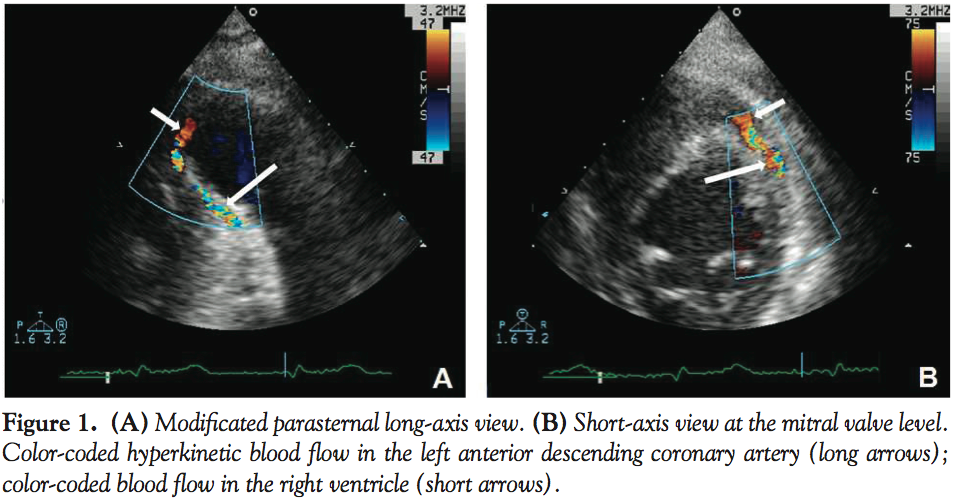

Two days after the index event, subsequent ST elevation +4.0 mV in leads V3-V4 and troponin level of 8.1 ng/mL was observed with no angina symptoms. Transthoracic echocardiography documented akinesia of the left ventricular apical segments, middle segments of anterior wall, and intraventricle septum. Pathological blood flow along the left anterior descending (LAD) directed to the right chamber was also observed (Figures 1A and 1B). Diagnostic angiography identified a fistula from the left coronary artery (LCA) descending to the right ventricle (LAD-RV) with a steal phenomenon and TIMI 2 flow (Figure 2A). LAD-RV shunt was successfully sealed by a 26 mm polytetrafluoroethylene-coated stent graft. Procedure effect was optimal, with TIMI 3 flow (Figures 2B and 2C). The patient was discharged on the 25th day of hospitalization with no clinical evidence of RV failure or angina symptoms.